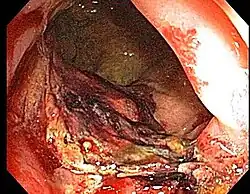

Proctitis or anusitis is an inflammation of the anus and the lining of the rectum, affecting only the last 6 inches of the rectum.

Doctors can diagnose proctitis by looking inside the rectum with a proctoscope or a sigmoidoscope. A biopsy is taken, in which the doctor scrapes a tiny piece of tissue from the rectum, and this tissue is then examined by microscopy. The physician may also take a stool sample to test for infections or bacteria. If the physician suspects that the patient has Crohn's disease or ulcerative colitis, colonoscopy or barium enema X-rays are used to examine areas of the intestine.